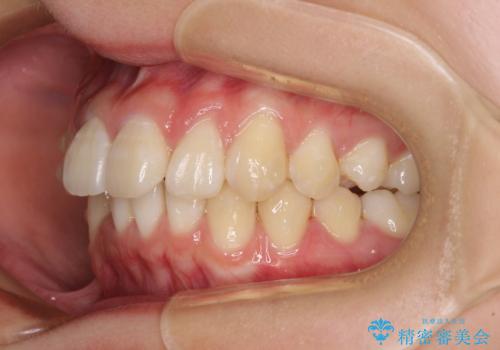

上下前歯の叢生をインビザラインできれいに

- 前歯のデコボコを気にして来院された患者様です。

前歯が重なっていることで口元が閉じにくくなっていたため、歯列全体の側方への拡大と、歯と歯の間を少し削ってスペースを獲得することとしました。